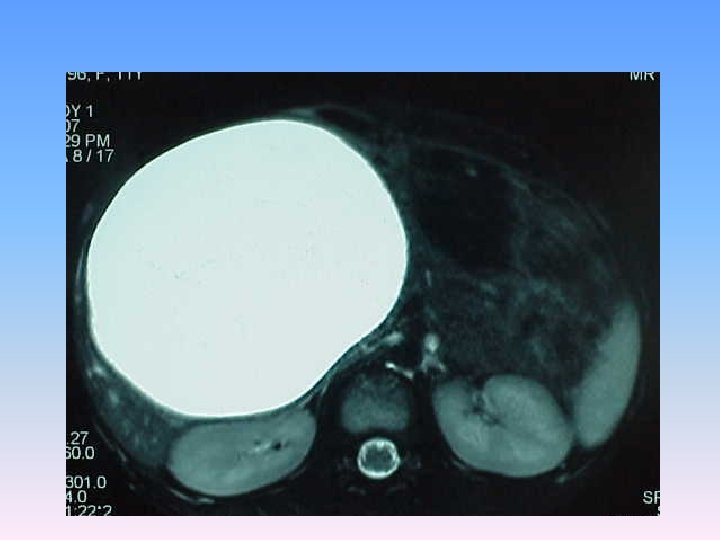

Abdominal CT Scan § A regular lobulated cystic mass in right lobe of liver (120 x 120) without calcification causing dilatation of intra & extra biliary ducts.

MRCP & MRI § Huge thicked wall cystic mass (140 x 120 mm), at the portahepatis that seems connected to biliary tree and gall bladder, resulted in severe dilatation of intra hepatic bile ducts and displaced right kidney posteriorly. § Spleen, kidneys, bowel loops and abdominal wall are normal. § Finding could be due to congenital anomalies like choledocal cyst, Duplication cyst, mesenteric cyst and hydatid cyst are in DDx.